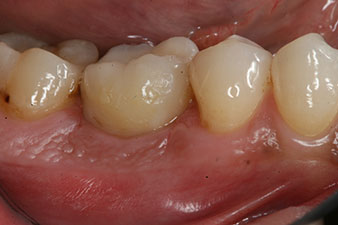

Последните снимки показват закрепената с винт монолитна композитна корона на място и рентгеновата проверка (фиг. 9 и 10) (6).